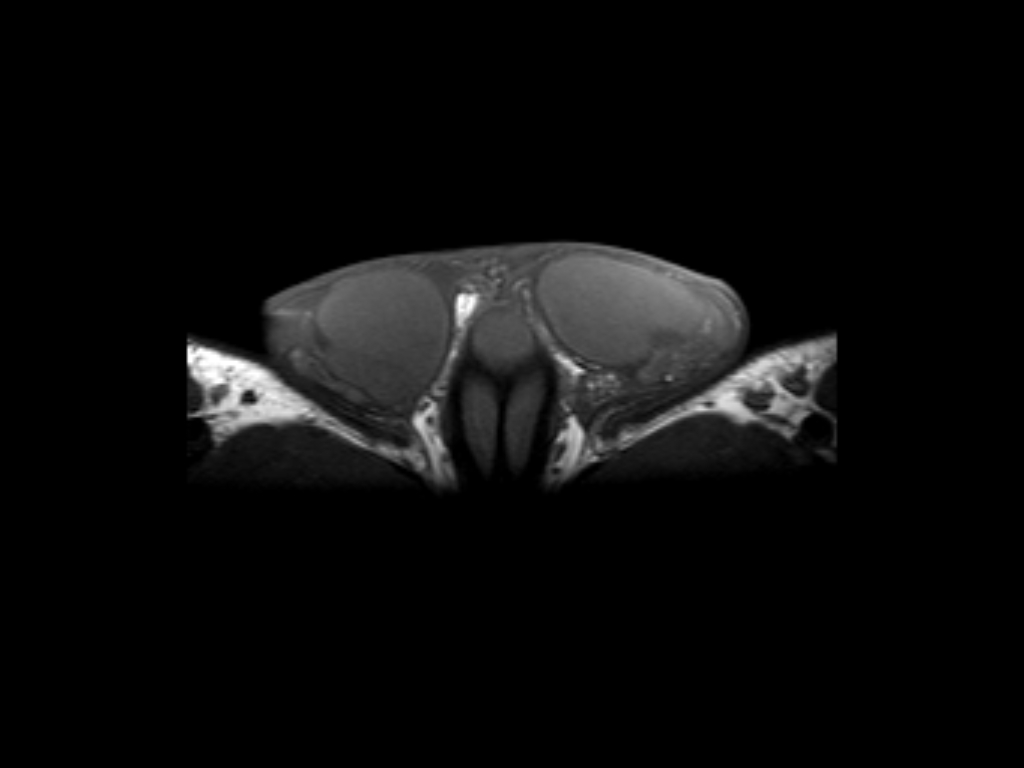

Χαρακτηριστικές Εικόνες MRI Οσχέου

ii) T1W SE

Βασική Ακτινοανατομία MRI Οσχέου